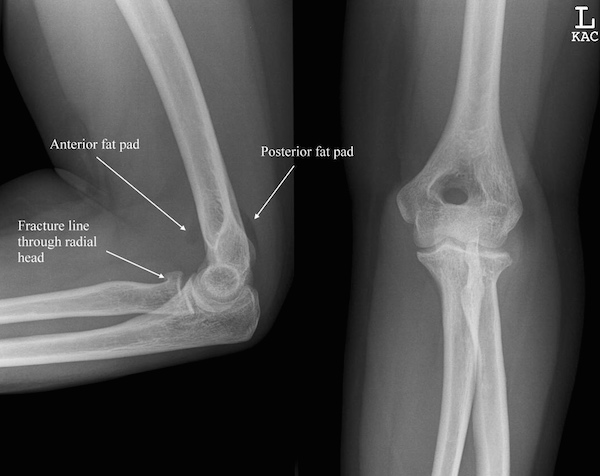

RADIAL HEAD FRACTURES

What are Radial Head Fractures?

The elbow joint is made up of three bones, the humerus, ulna, and radius. The Radius is positioned laterally in the forearm and lies next to the Ulna. When the elbow is flexed the proximal part of the radius or head articulates with a rounded projection of the humerus or the capitulum. The elbow joint is involved with the twisting motions of the forearm (supination/pronation) via the motion of the radial head. As the forearm rotates, the radial head twists it is “held in place” by the annular ligament. A radial head fracture site can limit elbow function or depending on severity lead to complete non-functionality.